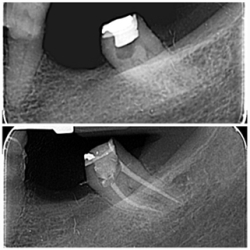

Endodontski zahvat predstavlja liječenje korijenskih kanala zuba s ciljem očuvanja zuba u usnoj šupljini. Postupak podrazumijeva vađenje, odstranjivanje pulpe zuba iz kanala, čišćenje i ispiranje korijenskih kanala posebnim ručnim ili strojnim iglicama i tekućinama za ispiranje koje odstranjuju zaostale bakterije i upalne produkte i dezinficira kanale. Sam postupak je bezbolan jer ga radimo uz primjenu anestezije. Suvremena endodoncija se zalaže za jednoposjetnu endodonciju, što podrazumijeva da se cijeli postupak napravi u jednoj posjeti.

Kod nas u ordinaciji koristimo VDW RECIPROC SILVER moderni uređaj za strojnu endodonciju, te uređaj za precizno mjerenje duljine kanala (endometar). Oni nam omogućuju vrhunske rezultate kao i liječenje zuba u jednoj posjeti što ručnim tehnikama i iglicama nije moguće napraviti. Završno punjenje se provjerava RTG snimkom.